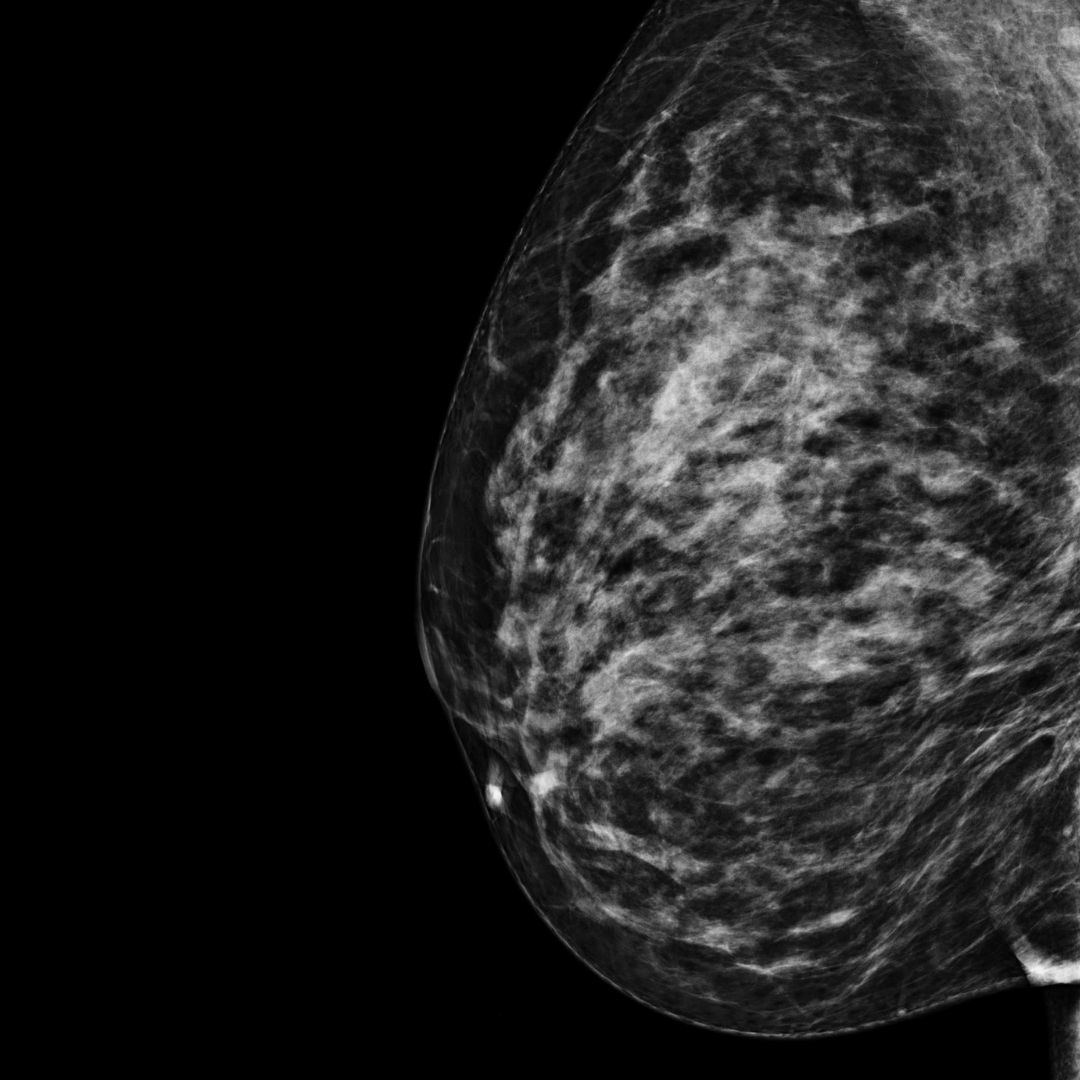

Category C

BI-RADS category C:

The breast tissue is mostly fibroglandular tissue with some areas of fatty tissue. The breast tissue is dense.